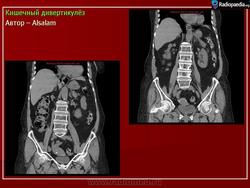

Кишечный дивертикулёз. Пнд, 09/09/2013 - 22:01 #1 Катенёв Валенти... Не на сайте Был на сайте: 7 лет 5 месяцев назад Зарегистрирован: 22.03.2008 - 22:15 Публикации: 54876 Дивертикулёз сигмы и нисходящей ободочной кишки Fig.23.: Radiographic image: multiple, round filling defects are seen on the sigma and on the descending colon. Втр, 11/11/2014 - 13:06 #2 Катенёв Валенти... Не на сайте Был на сайте: 7 лет 5 месяцев назад Зарегистрирован: 22.03.2008 - 22:15 Публикации: 54876 Продолжение. Приложения:

Дивертикулёз сигмы и нисходящей ободочной кишки